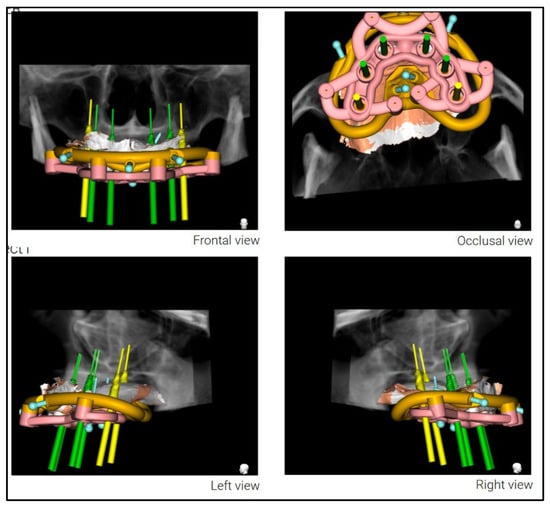

A stackable surgical guide system with magnetic retention was planned and fabricated. The guide set included a mucosa-supported base guide, an implant guide, and a multifunctional prosthetic verification guide. A flapless surgical approach was used. After base guide stabilization, the magnetic implant guide was sequentially positioned for each osteotomy. All six implants were placed according to the digital plan, achieving primary stability. Multi-unit abutments were installed to support immediate loading (Figure 8 and Figure 9).

Figure 8.

Planning of the surgical guide with magnetic retention using Real GUIDE Universal Open Systems.

Figure 9.

Multifunctional prosthetic verification guide—occlusal view—ensuring correct placement of the dental implants in relationship with the provisional restoration.

By integrating CBCT imaging with high-resolution surface scans, the digital workflow enabled precise visualization of the bone, soft tissues, and proposed restorations [,]. This multidimensional diagnostic environment supported a prosthetically guided surgical plan that was fully transferable to the clinical setting through the use of a stackable guide system. Beyond calibrated 2D photographs, contemporary platforms allow import of 3D facial scans, enabling a fully digital ‘virtual patient’ in which CBCT, intraoral scans, and facial soft-tissue geometry are co-registered. Such volumetric datasets improve control of midline, smile arc, and incisal display across expressions and can further reduce intraoperative adjustments by anchoring the stackable sequence to a more robust esthetic reference.

Stackable surgical guides, composed of modular components for adaptation, bone reduction, implant osteotomy, and prosthetic loading, minimize cumulative deviation in full-arch rehabilitation. As shown in this case and corroborated by the recent literature [,,,], these systems offer a highly accurate, efficient, and reproducible pathway for immediate loading. The magnet-based modular guide used here allowed for stable and flexible transitions between surgical stages, reducing chair time and increasing surgical confidence [,,,,].

Each component of the guide system was digitally fabricated using a comprehensive CAD/CAM protocol. The initial design workflow was performed in Real GUIDE Universal Open, with STL exports refined in Meshmixer (Autodesk, San Francisco, CA, USA). Retentive and anti-rotational features—including cylindrical guide housings and embedded neodymium magnets (5 × 1 mm)—were digitally incorporated to ensure precise repositioning and secure coupling of components.

The guides were oriented in PreForm (Formlabs, Somerville, MA, USA) and printed using a Formlabs 3B+ Dental SLA printer with biocompatible Surgical Guide Resin V1. Post-processing adhered strictly to manufacturer recommendations, including dual-stage isopropyl alcohol washes, air drying, and final light curing (30 min at 60 °C and 405 nm). Manual finishing was completed using rotary instruments, and magnet housings were cemented using dual-cure self-adhesive resin cement (Calibra Universal, Dentsply Sirona). Metal sleeves compatible with the implant system were press-fitted into the osteotomy channels to guide drilling and implant placement with maximum precision [,,,,].